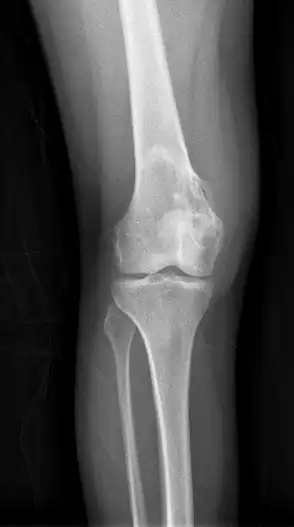

| Enchondroma[2] |

| |